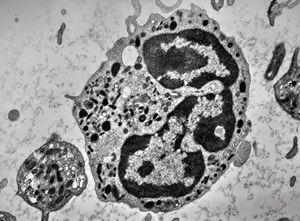

F,61y. | blood - eosinophilic granulocyte

blood … eosinophilic granulocyte

M,66y. | bone marrow - eosinophilic granulocyte